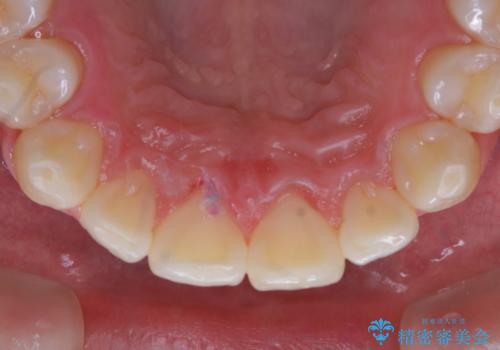

日々の磨き残しをPMTCできれいに

そのため、歯科医院にて定期的に歯磨きのチェックや専門的な機械でのクリーニングをすることが大切です。